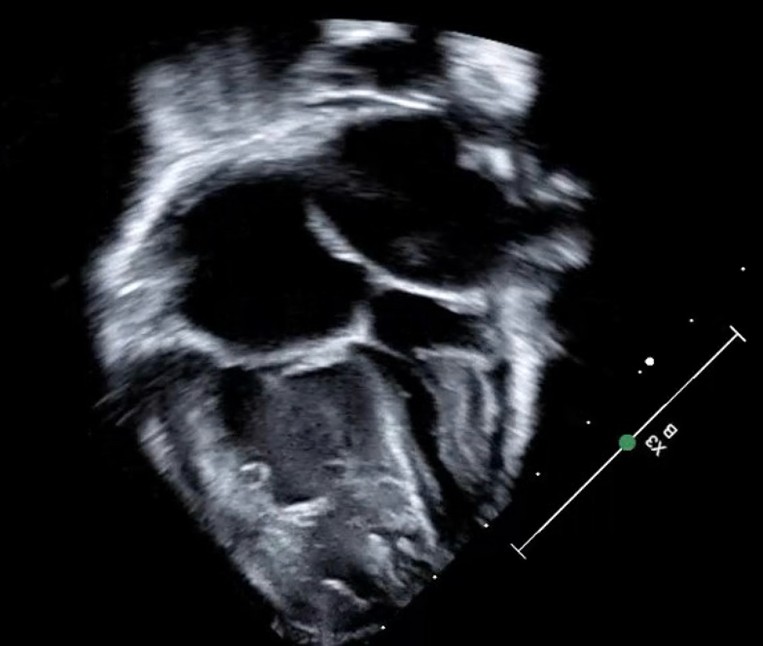

A 5kg, 4-month-old infant with feeding intolerance and failure to thrive is noted to have a murmur on pediatrician follow up visit. A 4-chamber view of his transthoracic echocardiogram is shown below. What is the MOST LIKELY diagnosis identified in this image?

Cor triatriatum (from the Latin for a “heart with three atria”) is a rare cardiac anomaly that results from abnormal septation of either the right (dexter – from the Latin for “right-sided or right-handed”) or left (sinister – from the Latin for “left-sided or left-handed”) atrium. It occurs in less than 0.1% of all congenital heart disease. In classic cor triatriatum sinister (CTS), which was present in the patient above, a fibromuscular membrane divides the proximal atrium, which accepts pulmonary venous return, from the distal atrium which contains the atrial appendage and mitral valve. The membrane may be complete, incomplete, or fenestrated. The severity of the membrane gradient, and presence or absence of other cardiac anomalies, will determine the age and status at presentation.1

The image in the scenario clearly shows a left atrial membrane, effectively separating it in proximal and distal portions. Cor triatriatum dexter would result from a right atrium membrane, and no membrane would be seen in context of pure mitral stenosis.